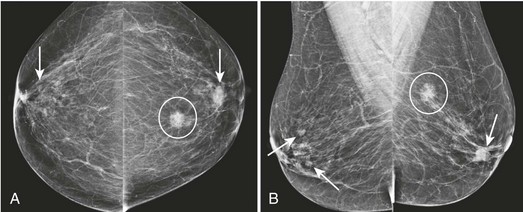

FIGURE 8-1 Multiple Bilateral Benign Masses.

Screening mammogram on a 48-year-old woman showing multiple bilateral similar-appearing masses with partially circumscribed margins. This woman had bilateral cysts previously demonstrated by US. There were no suspicious changes compared with previous mammograms. The patient was assigned BI-RADS 2, and no suspicious changes have occurred in over 2 years on subsequent mammography.